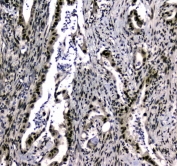

IHC testing of FFPE human colon cancer tissue with UBA2 antibody at 1ug/ml. Required HIER: steam section in pH6 citrate buffer for 20 min and allow to cool prior to staining.